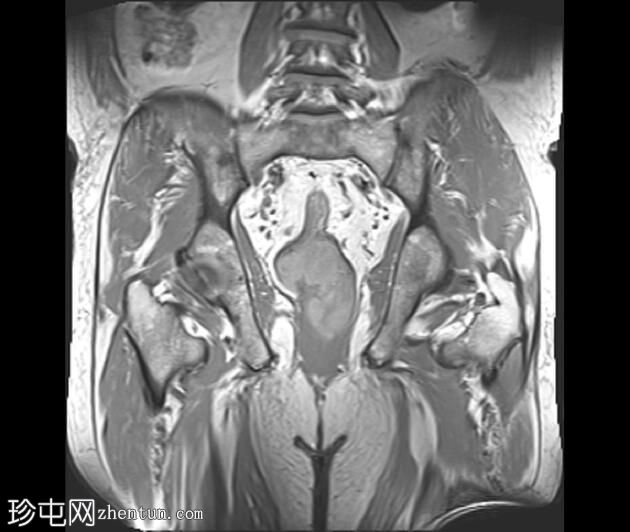

冠状位

T2加权像

可见一不规则分叶状肿块,累及直肠中段和远端,头尾方向长约7 cm,下缘距肛缘约2.5 cm。在T1加权像和T2加权像上,该病灶相对于骨骼肌均呈高信号。 PDFS(脂肪抑制)图像显示持续高信号强度,提示存在黑色素和/或出血成分。

增强扫描显示病灶内呈不均匀强化。直肠下段7点钟位置的系膜筋膜受累。后方系膜可见少量淋巴结。未见邻近器官侵犯。